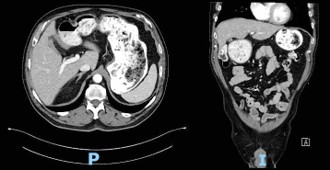

Computed Tomography (CT) scan performed at the time of admission revealed abundant food content with organized appearance in the abdomen (Figure 1), which was morphologically similar to that observed in previous CT scans. The findings supported chronic food retention with difficulty in gastric emptying at the level of pyloric antrum. Pharyngo-esophageal study revealed the presence of a bezoar occupying the entire gastric chamber with normal esophageal motility (Figure 2).

Figure 1: Computed tomography scan at time of admission.